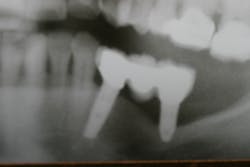

The expense and technical difficulty of removing an implant, rebuilding the defect, and replacing the failed dental implant with a new one can often be challenging. In addition, regenerative treatments for dental implant repair can be both costly and unpredictable if not done correctly (figures 1–3). Long-term maintenance and clinical oversight of peri-implant disease remains the most cost-effective and successful preventive measure for treating this disease.8 If this AI technology helps to determine the failure risk for the patient after surgical repair of the diseased dental implant, explantation with the replacement of a new implant or fixed/removable prosthesis may offer a better treatment alternative.